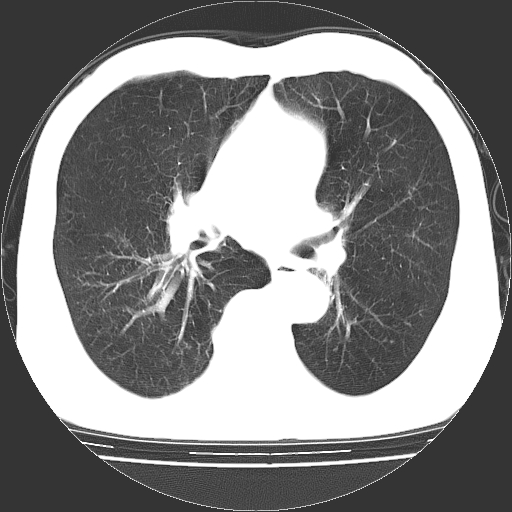

以下是引用hhcckk在2009-1-1 15:38:00的发言:[br]左下肺少许絮状模糊影--考虑感染[br]两肺散在小点状密度增高影--结合病史考虑矽肺?[br]气管壁钙化--可能由于老年退变性引起的